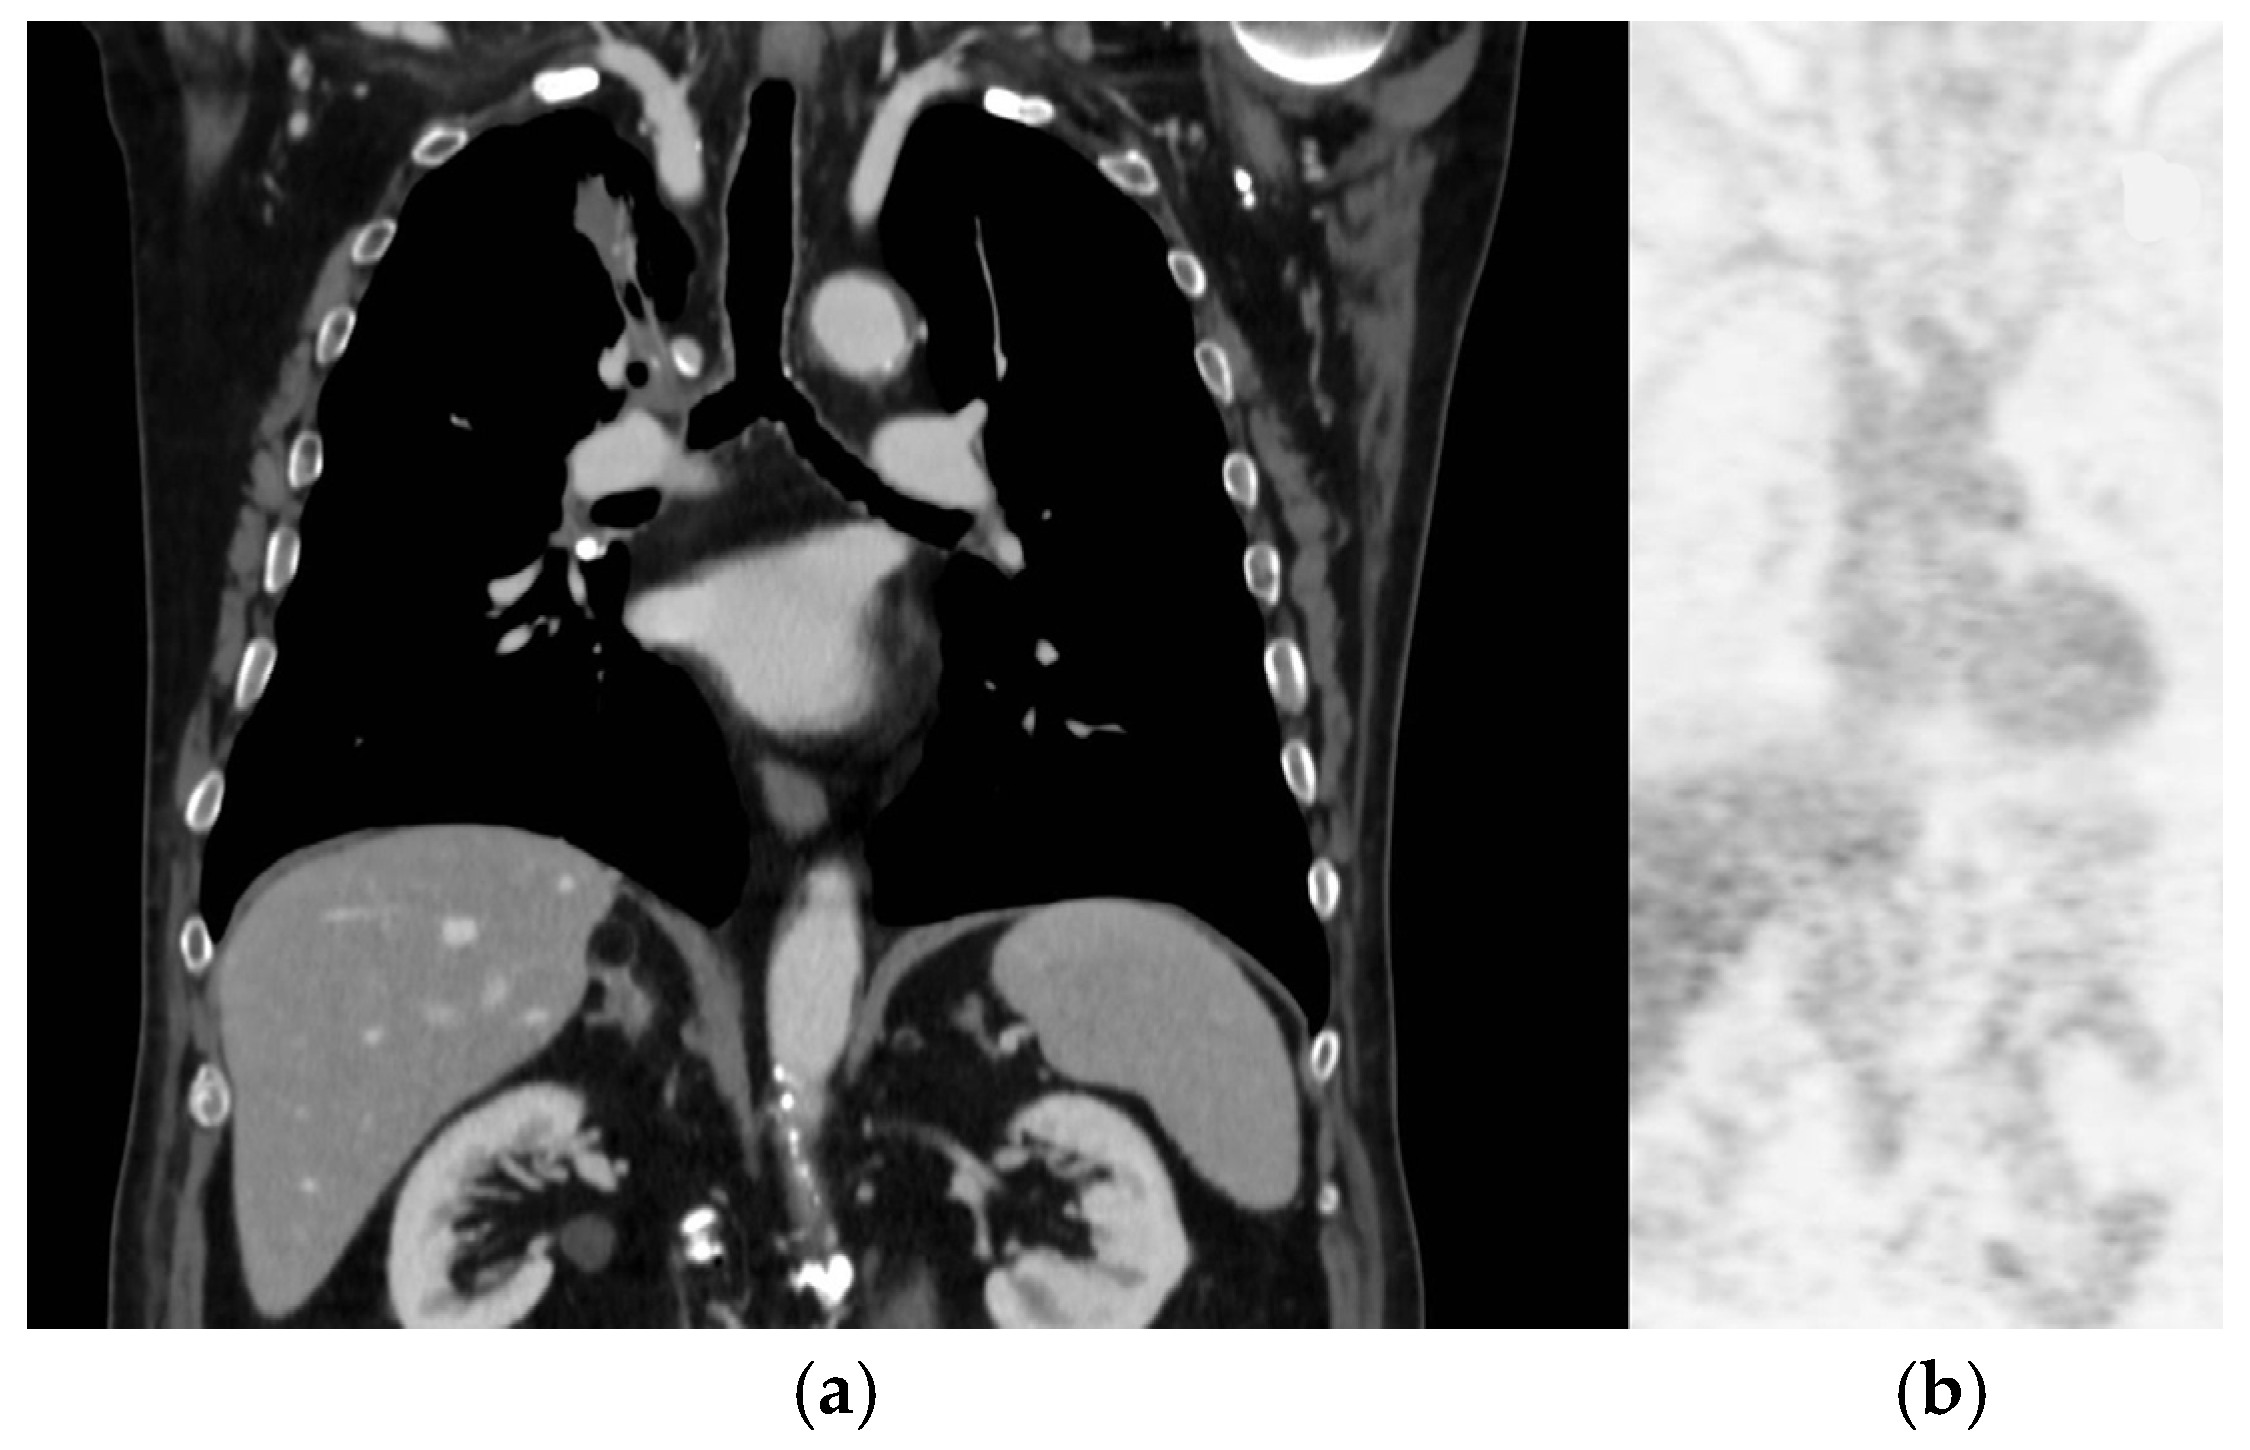

2. Case Report